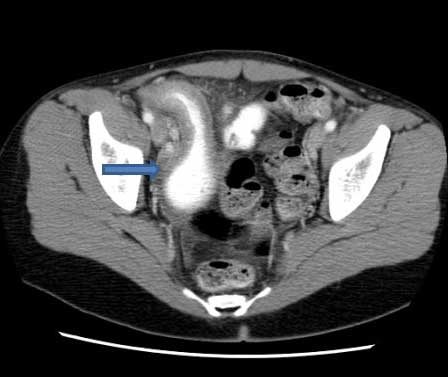

Abdominal CT scan with oral and intravenous contrast to look for small-bowel lymphoma, Crohn's disease, or pancreatic abnormalities.[Figure caption and citation for the preceding image starts]: CT scan demonstrating thickening of the terminal ileum in a patient with Crohn's disease exacerbationCourtesy of Drs Wissam Bleibel, Bishal Mainali, Chandrashekhar Thukral, and Mark A. Peppercorn; used with permission [Citation ends].

[Figure caption and citation for the preceding image starts]: CT scan demonstrating thickening of the terminal ileum in a patient with Crohn's disease exacerbationCourtesy of Drs Wissam Bleibel, Bishal Mainali, Chandrashekhar Thukral, and Mark A. Peppercorn; used with permission [Citation ends].